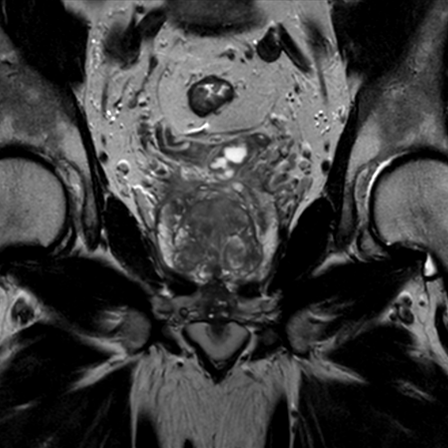

Prostate imaging with dS Endo + dS Torso coil

• Clinical Application